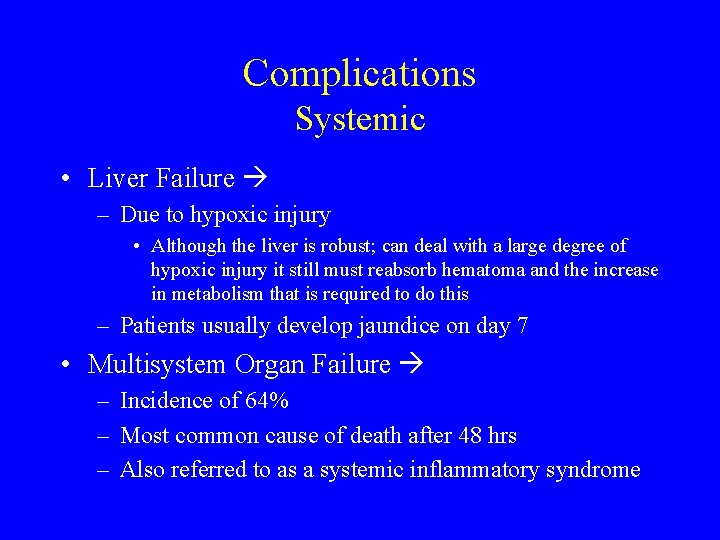

Complications Systemic • Liver Failure – Due to hypoxic injury • Although the liver is robust; can deal with a large degree of hypoxic injury it still must reabsorb hematoma and the increase in metabolism that is required to do this – Patients usually develop jaundice on day 7 • Multisystem Organ Failure – Incidence of 64% – Most common cause of death after 48 hrs – Also referred to as a systemic inflammatory syndrome